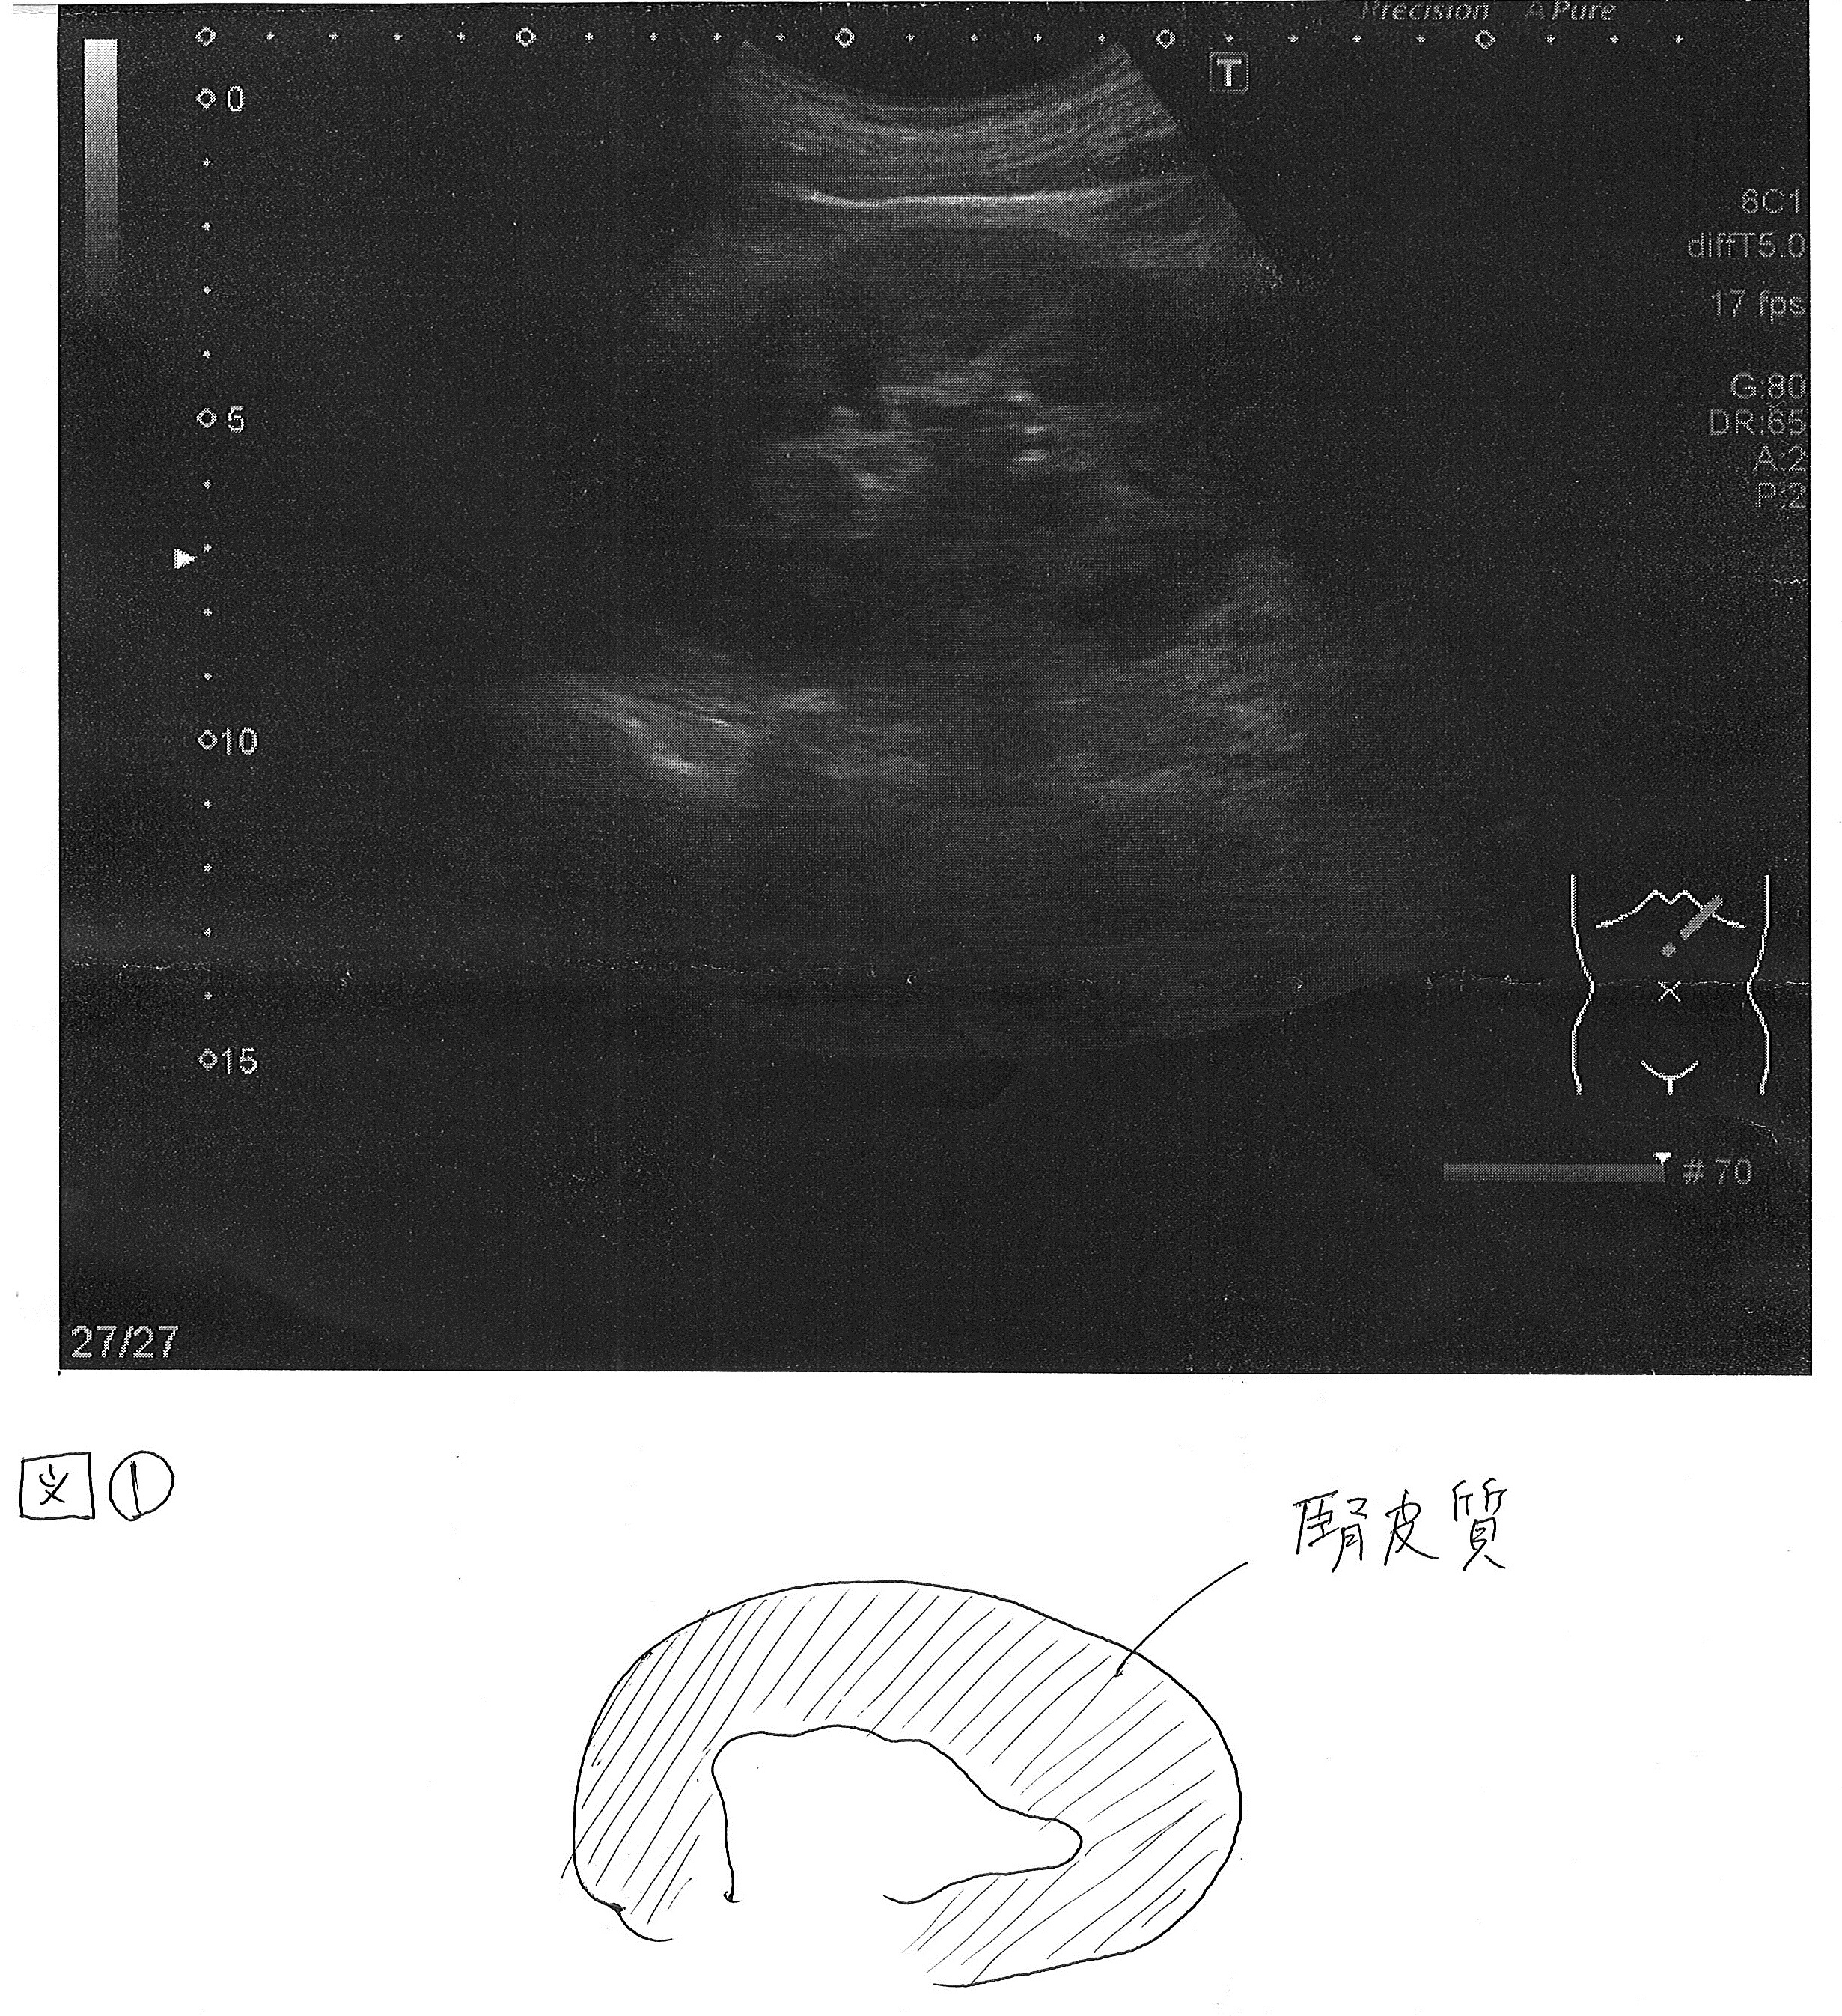

インスリンボール(インスリン由来アミロイドーシス):注射したインスリンがアミロイド蛋白という物質になって皮膚の下に沈着することにより、皮膚の下に少し硬いしこりのようなものができることが多いです。(図1)

図2はインスリンボールができた皮膚にインスリンを注射した時と正常な皮膚にインスリンを注射した時に血液中のインスリン濃度を示しています。

インスリンボール(腫瘤)がある皮膚に10単位のインスリンを注射してもほとんど吸収されていないことが解ります。

先程お話ししたように患者さん自身は気付かないことがあり、インスリン注射をしている患者さんは年1回スタッフに皮膚を見てもらうといいと思います。また、最近では皮膚エコー検査によって触ってもわからない皮膚変化を発見することができます。当院でも行っていますが、検査に時間がかかる為、入院患者さんに行っています。